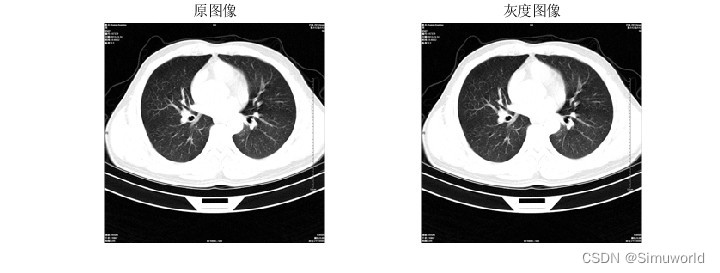

本文介绍了基于分水岭分割算法的肺癌诊断系统,通过MATLAB进行仿真。首先,对CT图像进行预处理,然后运用分水岭算法进行分割,提取肺部区域。接着,通过特征提取和机器学习分类实现肺癌的自动诊断。算法原理包括图像平滑、梯度计算、形态学处理和分水岭变换。